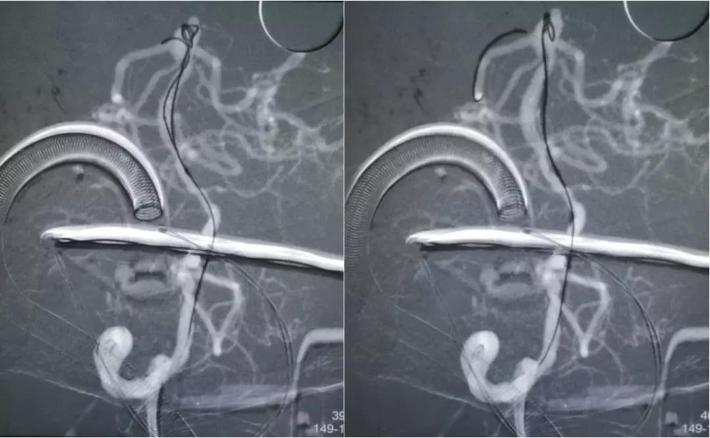

拟通过微导丝将支架微导管预置到右侧大脑后动脉,但微导丝支撑力不足,直接通过基底动脉至右侧大脑后动脉较困难,先在动脉瘤腔内部分填塞弹簧圈(4mm*10cm),以作支撑,再将微导丝带微导管置入右侧大脑后动脉,经微导管送入LEO支架(2.5*18mm)

采用支架半释放技术,LEO 2.5*18mm半释放,继续送入编框圈编框成篮,再依次填入填充圈